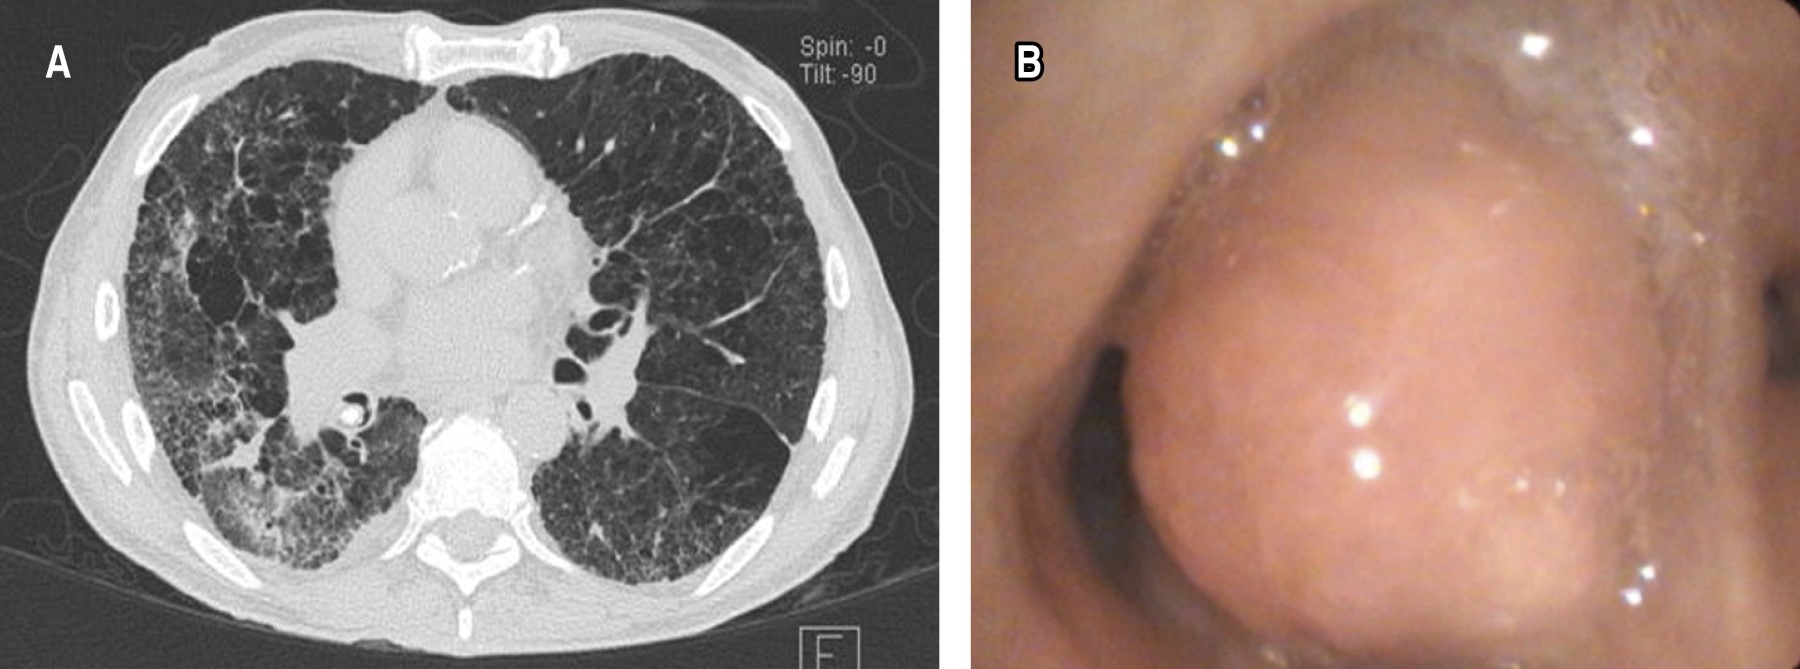

Tumor endobronquial se identificaron 64, la localización más frecuente fue en el árbol bronquial derecho, con 39 (60.9%) pacientes. De éstos, 19 (29.6%) se encontraron entre los segmentos 6 a 10 derecho, 12 (18.7%) en el lóbulo medio y ocho (12.5%) en los segmentos 1 a 3. En el árbol bronquial izquierdo, se observaron 25 casos (39%). De éstos, seis (9.3%) se encontraron entre los segmentos 6 a 10 izquierdo, 10 (15.6%) en la língula y nueve (14%) en los segmentos 1 a 3 (Figuras 1 y 2).